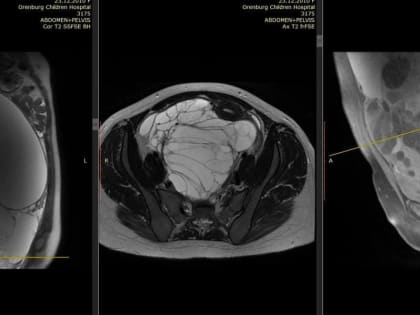

В Оренбурге удалили гигантскую опухоль у 13-летней девочки

Хирурги провели сложную операцию по удалению опухоли весом 8 кг.